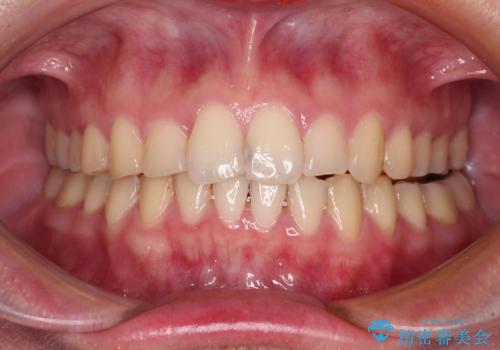

- 食いしばりが気になっていたとのことで来院された患者様です。

当初は睡眠時のマウスピースのみの製作をご希望でしたが、矯正治療の提案をしたところ、インビザラインにて矯正治療を行うこととなりました。

矯正治療中に食いしばりがより強くなることがあるため、半年に1回のペースでボツリヌストキシンによる咬合力緩和を並行して行うこととしました。

咬合力の緩和と食いしばりがちな咬み合わせが改善され、顎の負担が大幅に軽減されました。